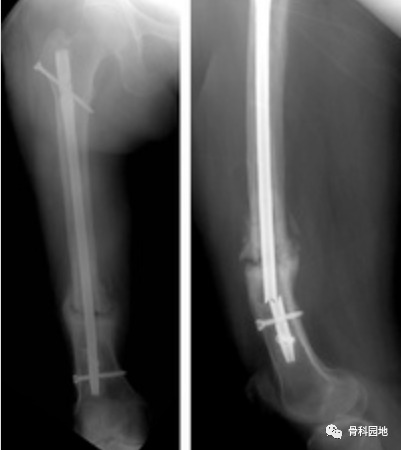

从长骨干取除断裂的髓内钉仍然是一个棘手的问题。本文介绍一种方法,该方法在技术上比文献中描述的其他方法要求低。此方法类似于钓鱼,这是一种通过鱼钩钓鱼的方法。在这种方法中,断裂的钉子在透视引导下钩住,并通过由不锈钢丝制成的钉钩以逆行方式取回。它无创地去除断裂的钉子,需要进一步暴露。1.首先钩子有一个宽阔的嘴,一个窄的弯曲(图A,B)。

2.逆行的方式钩住并取回钉子(图A,B)。

钓鱼技术用于取回髓内钉远端断裂部分。取了一根 20 号长的不锈钢线,其长度足以到达并取回断裂的钉子。如上所述,在其一端制作了一个钉钩。将去除的钉子近端部分用作模板,以按照所需的尺寸制作钩子。在透视引导下,钩子沿着髓管向下传递,然后穿过断裂的钉子,使得整个钩子位于钉子远端()。

然后将不锈钢丝拉近端以钩住断裂的钉子。然后通过轻轻地将不锈钢线拉出来取回钉子(图B)。